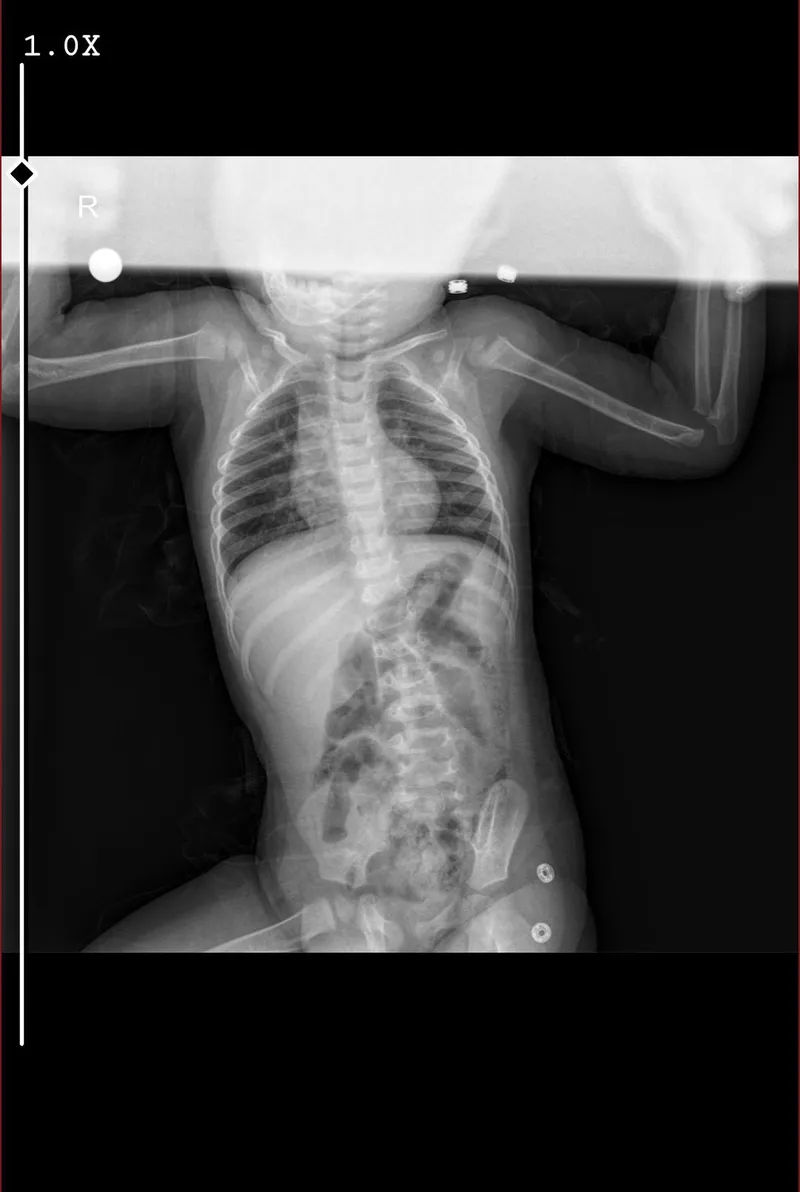

Klamoks iburamin zero ve asist kullandık geçmeyince tekrar acile gittik ve azro verdi budenosin ve ventosal verdi ama buharı mecbur kalmadıkça tıkanmadıkça verme dedi ne yapmalıyım şuan buharı düzenli olarak vermeli miyim ? 15 aylık erkek bebek 10.5 kilo

Bebeğinizin yaşadığı krup ve ciğer enfeksiyonu ciddi bir durumdur ve doğru tedavi yaklaşımı önemlidir.